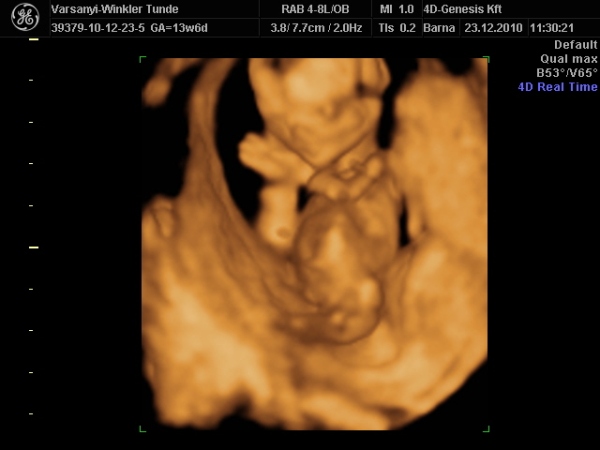

Bár tegnap a dokor bácsi azt mondta, hogy azért lassan vissza kellene vennem a lendületből, mert nem lesz jó vége. Manócska jól van, de tegnap nem tudtuk megnézni. Hasi uh-val próbálkozott, de pont úgy fordult, hogy csak a nagy kobakját láttuk